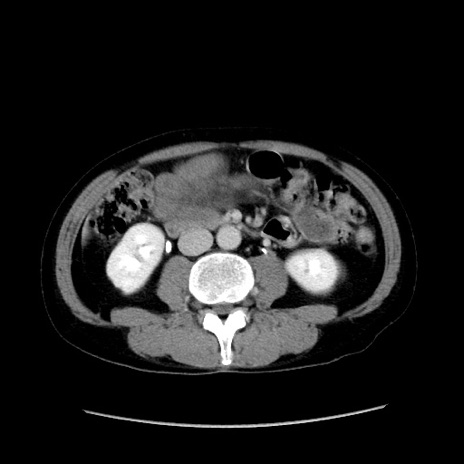

症例37(横断像)

【症例】40歳代 男性

【主訴】腹痛

【現病歴】4時間ほど前に電車に乗車中に臍部上より腹痛出現。徐々に増悪し起立困難となり、救急外来受診。生ものは数日食べていない。今朝お雑煮を食べた。

【身体所見】BT 36.8℃、BP 117/84mmHg、HR 91/min、SpO2 97%、苦悶様、腹部:臍上部広範囲圧痛あり、反跳痛±

【データ】WBC 8100、CRP 0.03